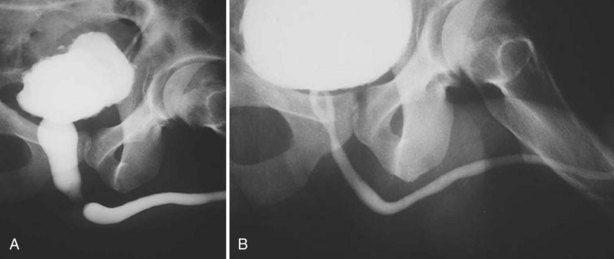

As with posterior urethral injury, a high index of suspicion must be maintained in all patients with blunt or penetrating trauma in the urogenital region, and urethrography should be performed in any case of suspected urethral injury (Husmann et al, 1993). Clinical signs of anterior urethral injuries include blood at the meatus, perineal hematoma, gross hematuria, and urinary retention. In severe trauma the Buck fascia may be disrupted, resulting in blood and urinary extravasation into the scrotum (Fig. 88–20 on the Expert Consult website).

Figure 88–20 A, Extravasation of contrast medium seen in scrotum on retrograde urethrogram in a patient with a straddle injury. B, Retrograde and antegrade urethrogram shows distal limit of urethral patency, but bladder neck does not open. C, Repeat antegrade urogram study showing proximal limit of urethral patency.

Armenakas and McAninch (1996) proposed a simple, practical classification scheme dividing anterior urethral injuries on the basis of radiographic findings into contusion, incomplete disruption, and complete disruption. Contusions and incomplete injuries can be treated with urethral catheter diversion alone. Initial suprapubic cystostomy is the standard of care for major straddle injuries involving the urethra (Park and McAninch, 2004); however, primary anterior urethral realignment has shown promising results with respect to stricture rate and erectile dysfunction in patients with straddle injuries of lesser magnitude (Ying-Hao et al, 2000; Yu et al, 2007).